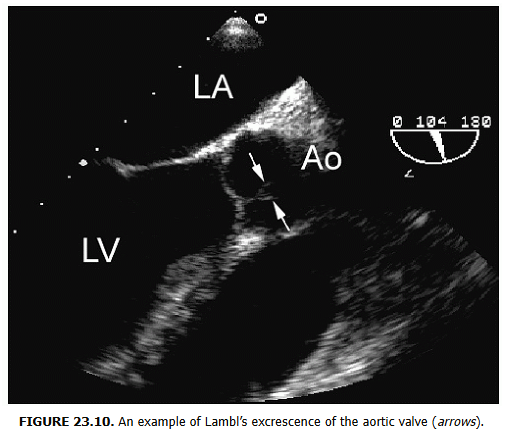

Lambl’s excrescence (LE)

Lambl’s excrescence (LE)는 1856년 V. D. Lambl이 처음 기술한 좌심방판막 접합선(coaptation line...